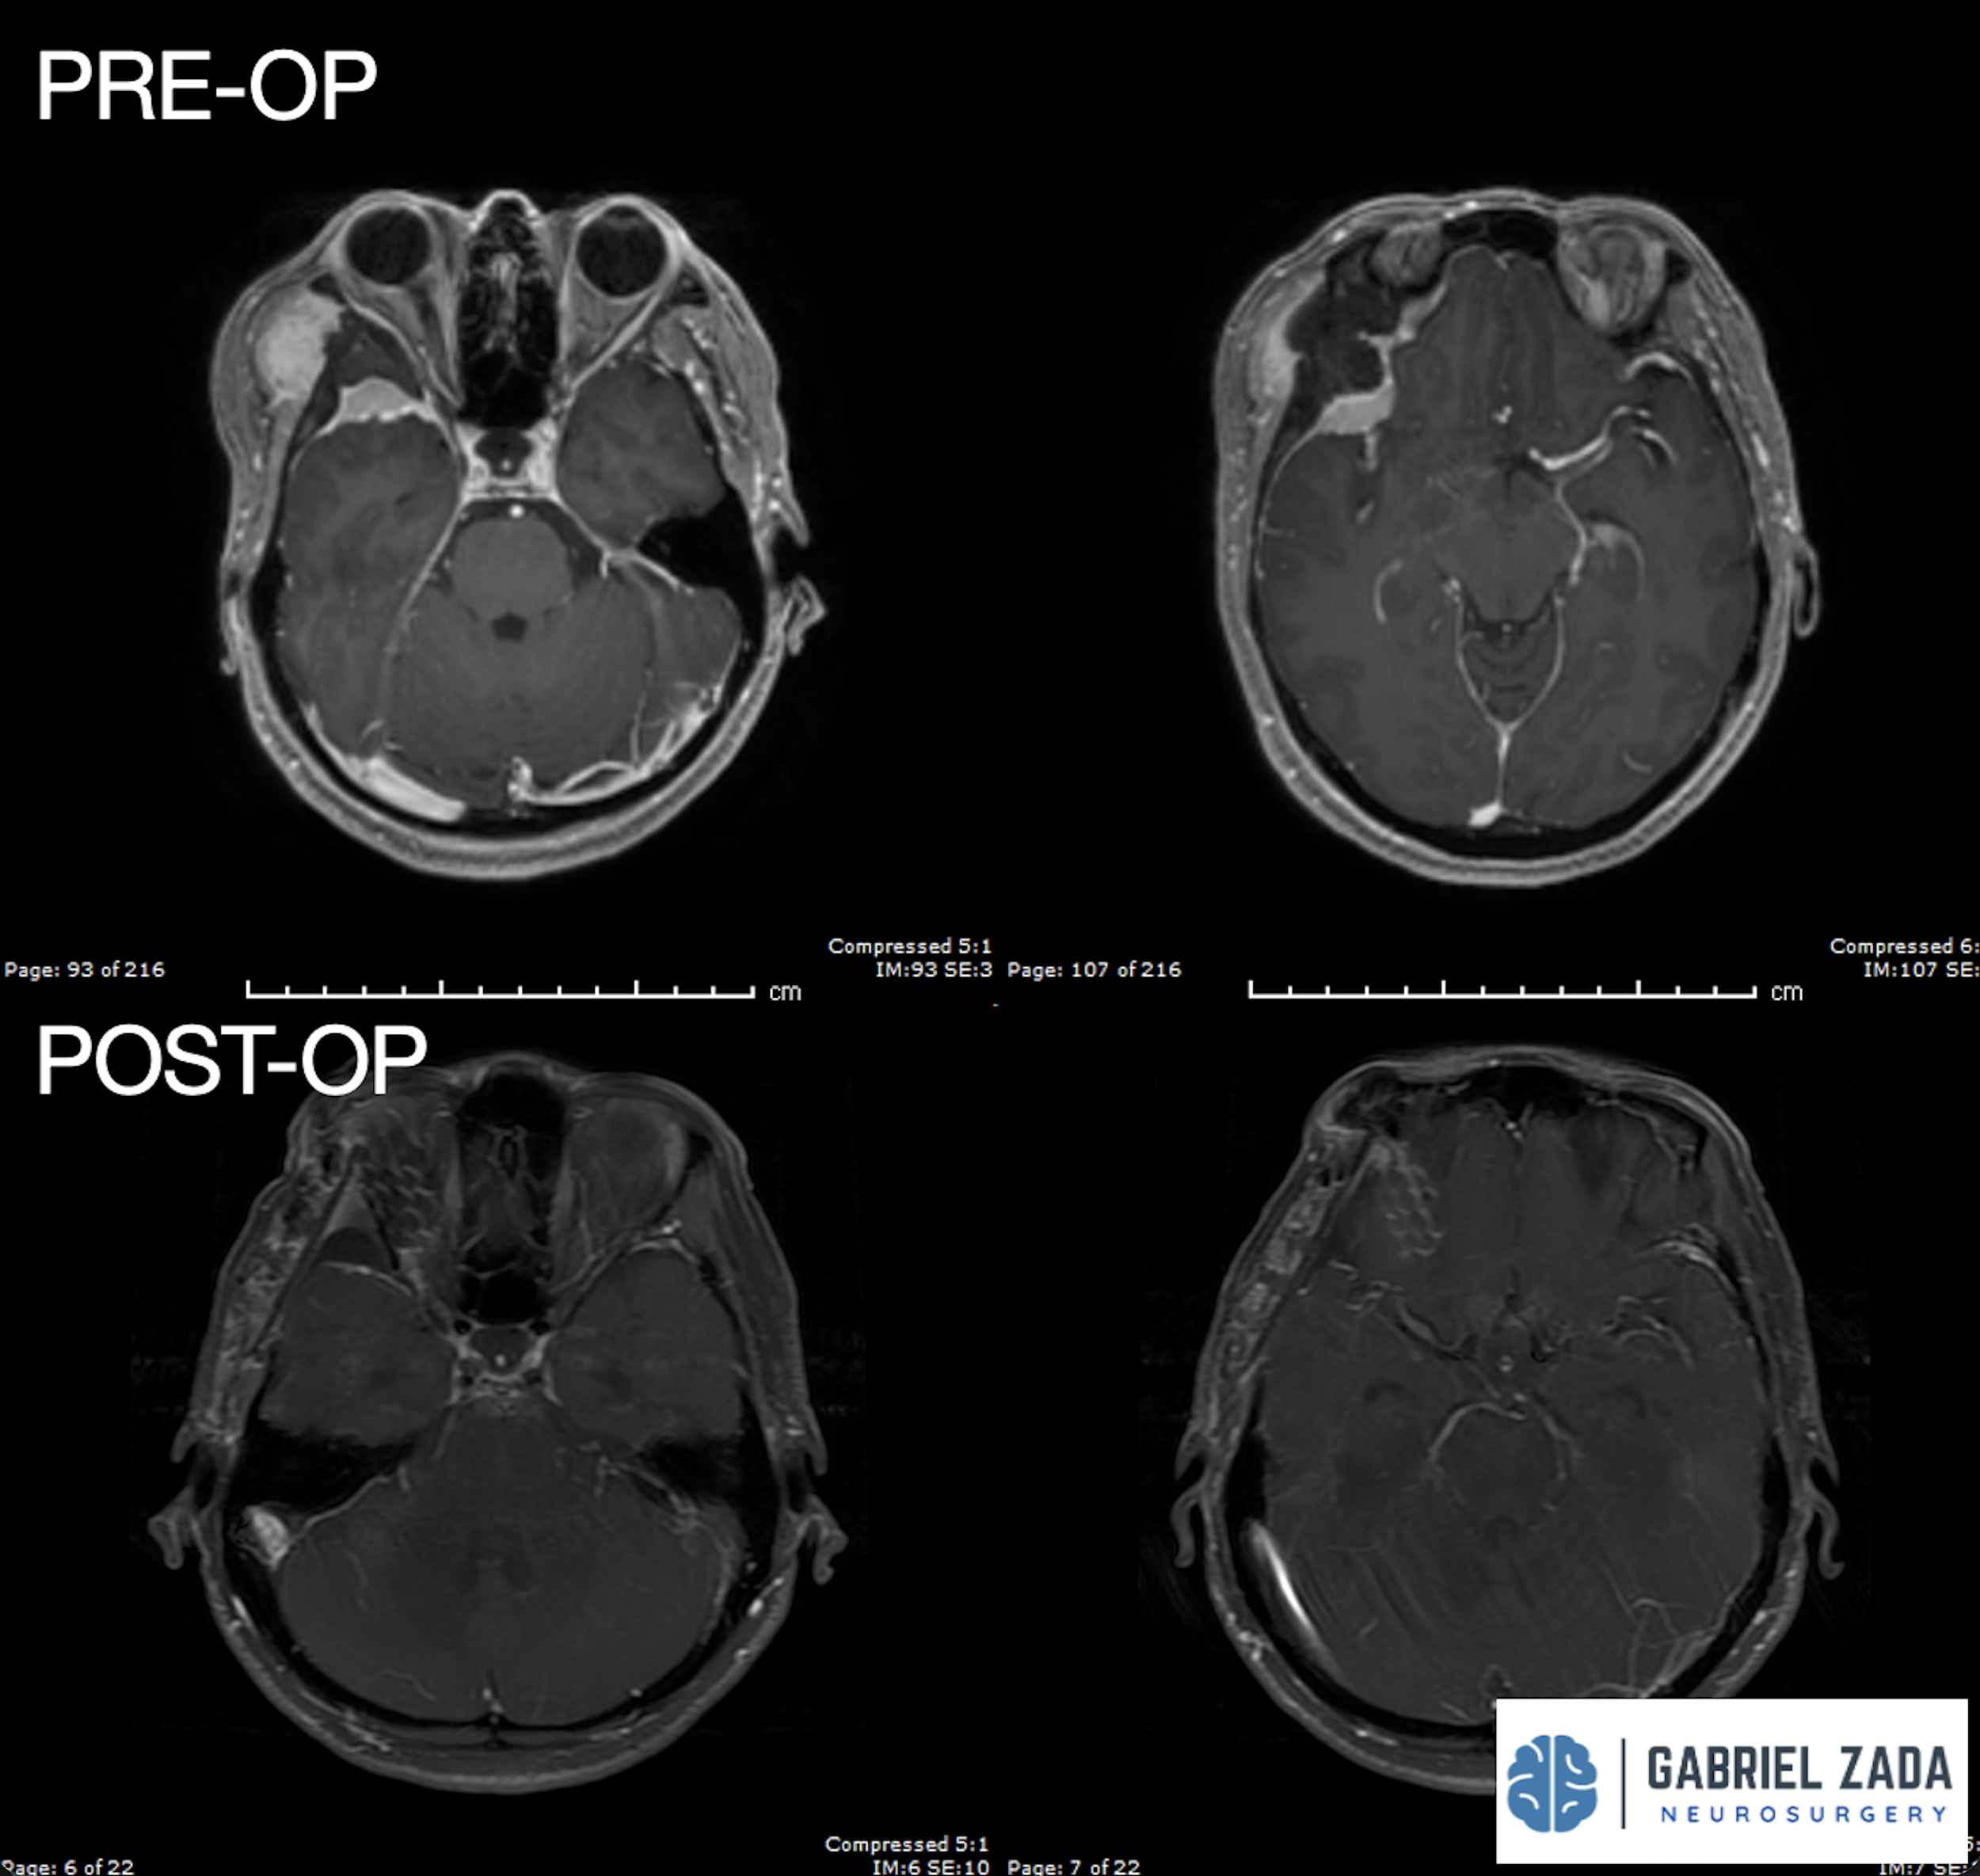

Explore this comprehensive gallery featuring pre‑ and post‑operative imaging of patients with skull‑base tumors treated by Gabriel Zada, MD, MS, FAANS, FACS. These cases highlight Dr. Zada’s expertise in advanced neurosurgical techniques and outcomes.

*Representative cases shown for educational purposes. All images de-identified. Individual results vary.